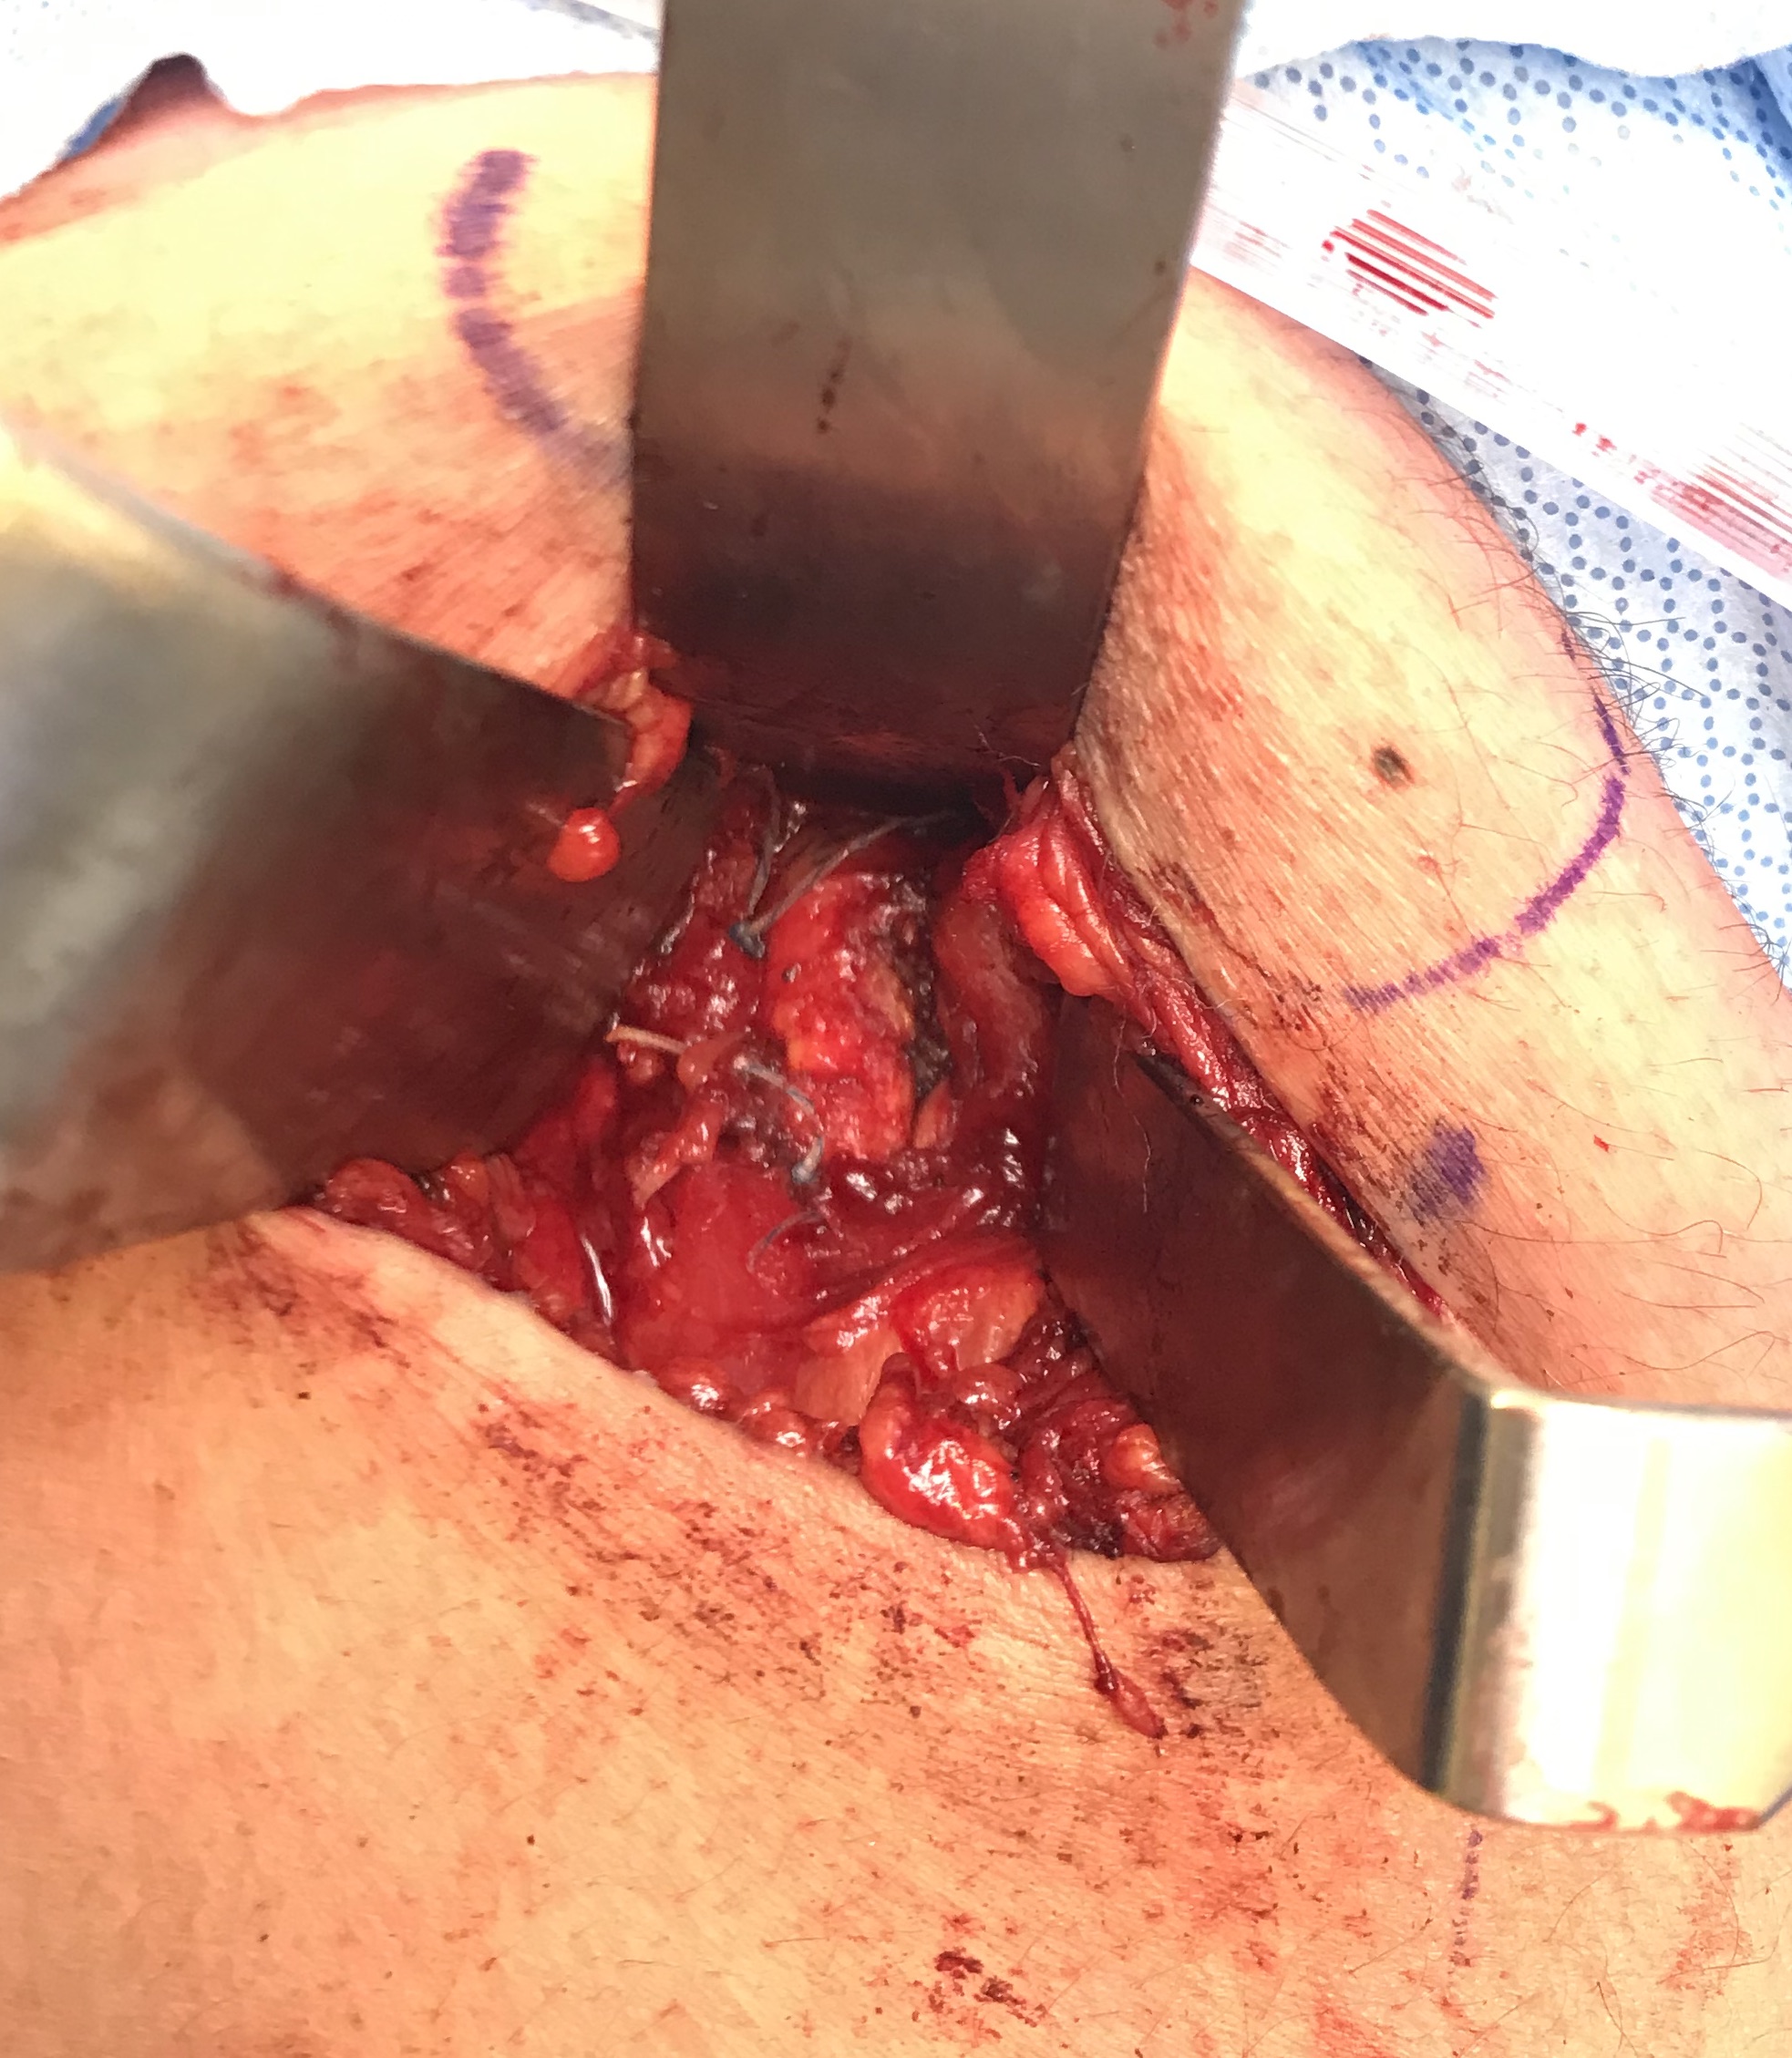

Post suture anchor repair

Ischial tuberosity exposed, then achilles bone block secured with screw

Pulvetaft weave tendon through the strongest, thickest part of the stump